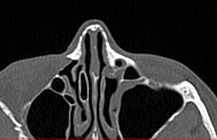

Преимуществом КТ является ее способность отлично визуализировать кости лицевого черепа, что делает методику незаменимой для оценки любых травматических повреждений носа, выявления аномалий развития носовой перегородки и, деформации хрящей.

Аппараты сканируют область исследования в течение нескольких секунд, производя одномоментно от 64 до 128 тончайших срезов толщиной от 0,5 мм. Высокая скорость сканирования обеспечивает минимальную дозу облучения для пациента. При этом получаются четкие изображения с высоким контрастным разрешением, что дает возможность рассмотреть исследуемую зону в мельчайших подробностях. Кроме того, томографы создают объемные 3D-изображения области носа и прилегающих пазух, что помогает в оценке пространственного соотношения анатомических структур, выявленной патологии и способствует проведению точной диагностики.

Что показывает КТ носа

- воспалительный процесс (утолщение слизистой оболочки, жидкость, признаки гноя);

- повреждение костей.